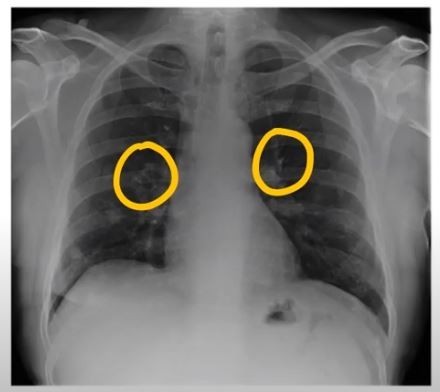

폐렴 증상 폐렴은 폐의 세균, 바이러스, 곰팡이 등 감염으로 인해

폐포(폐 속의 공기 주머니)에 염증이 생기고, 고름이나 액체가 차는 질환입니다.